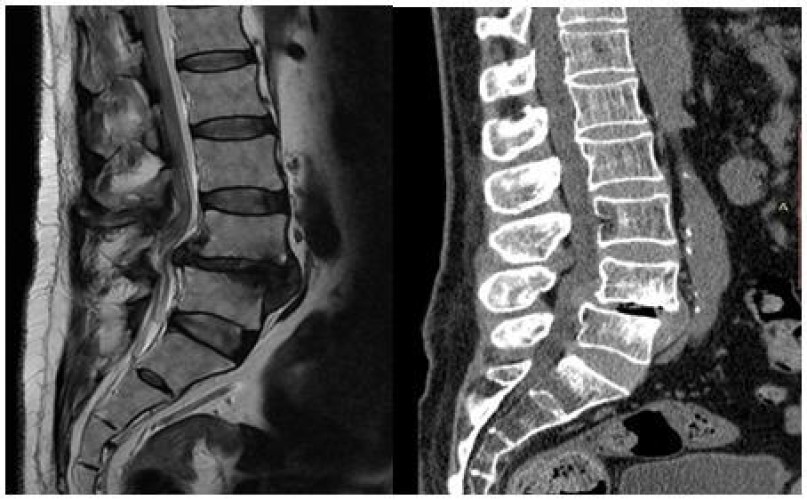

حيث تبين بعد مناظرة الأشعة المقطعية وأشعة الرنين المغناطيسي وجود تزحزح فقاري قطني مع كسر تحللي بعنق الفقرة القطنية الرابعة، مما أدى إلى ضغط شديد على جذور العصب النسئ بالطرفين الأيمن والأيسر.

وقد تكللت العملية ولله الحمد بالنجاح- وتمكّن المريض ولأول مرة منذ عامين المشي والحركة بدون ألم أو تنميل في الأطراف السفلية، حيث تم خلال العملية تثبيت الفقرات القطنية بواسطة مسامير تيتانيوم مع تركيب قفص تيتانيوم (إلمانية الصنع)، بهدف رفع الضغط عن جذور الأعصاب وتوسيع القناة العصبية القطنية وتوسيع مخارج جذور الأعصاب.